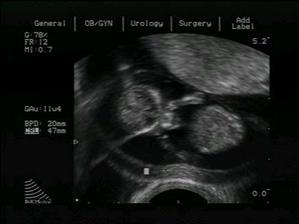

06.11.2007 - screening v I. trimestru - výsledek OK

13.01.2008 - velký UTZ - už víme, co to bude